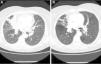

The patient was sent to our department in 2011 with chronic dry cough. Chest radiography revealed right hilar enlargement and atelectasis-partial condensation of the anterior segmental bronchus of the right upper lobe (RUL). Said findings were confirmed by chest CT, which also demonstrated bronchiectasis in the RUL and a right paratracheal adenopathy measuring 2cm (Fig. 1A). Given the suspicion for bronchial carcinoma, bronchoscopy was performed, which showed a middle lobe lobectomy stump with no signs of neoformation and an extensive black patch at the entrance of the bronchus of the left upper lobe. Due to an important amount of bleeding, only one biopsy sample could be taken. The tissue sample contained bronchial mucosa with macrophages in the lamina propria and black cytoplasmic pigment, with no signs of malignancy. The rest of the segmental bronchi of both lungs were impassable due to stenosis, especially in the adjoining airways near the black patch toward the culmen and the lingula. Isoniazid-resistant Mycobacterium tuberculosis was isolated in bronchial secretions.

The patient was treated for 6 months with ethambutol, pyrazinamide, and rifampicin. Afterwards, follow-up CT showed partial resolution of the infiltrate in the anterior segmental bronchus of the RUL with normalization of the size of the adenopathy (Fig. 1B). The endoscopic appearance was unchanged despite the treatment received. New bronchial suction and bronchoalveolar lavage samples confirmed the eradication of the Koch bacillus.